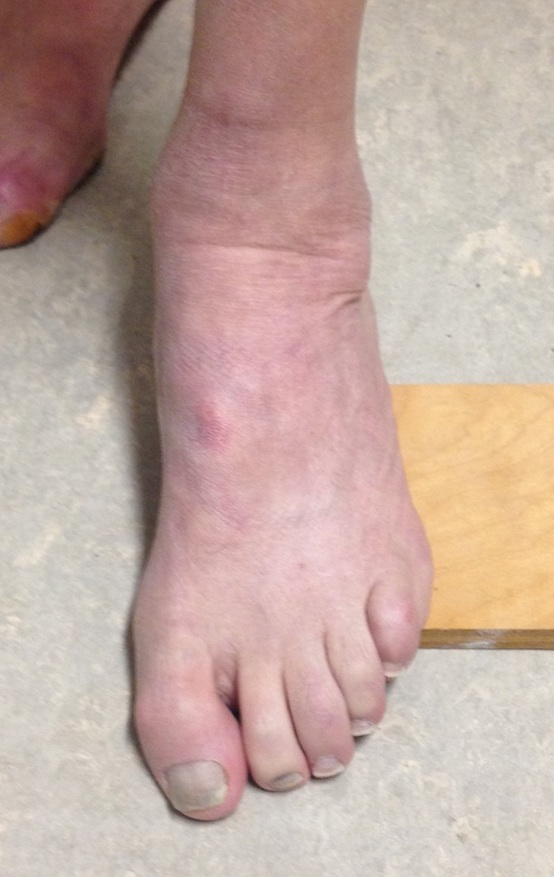

Cavus foot

Varus hindfoot

Coleman Block / Lateral Block Test

- block under lateral foot so first ray touches the ground

- eliminates forefoot deformity

- if hindfoot corrects the hindfoot is flexible

Correctable hindfoot